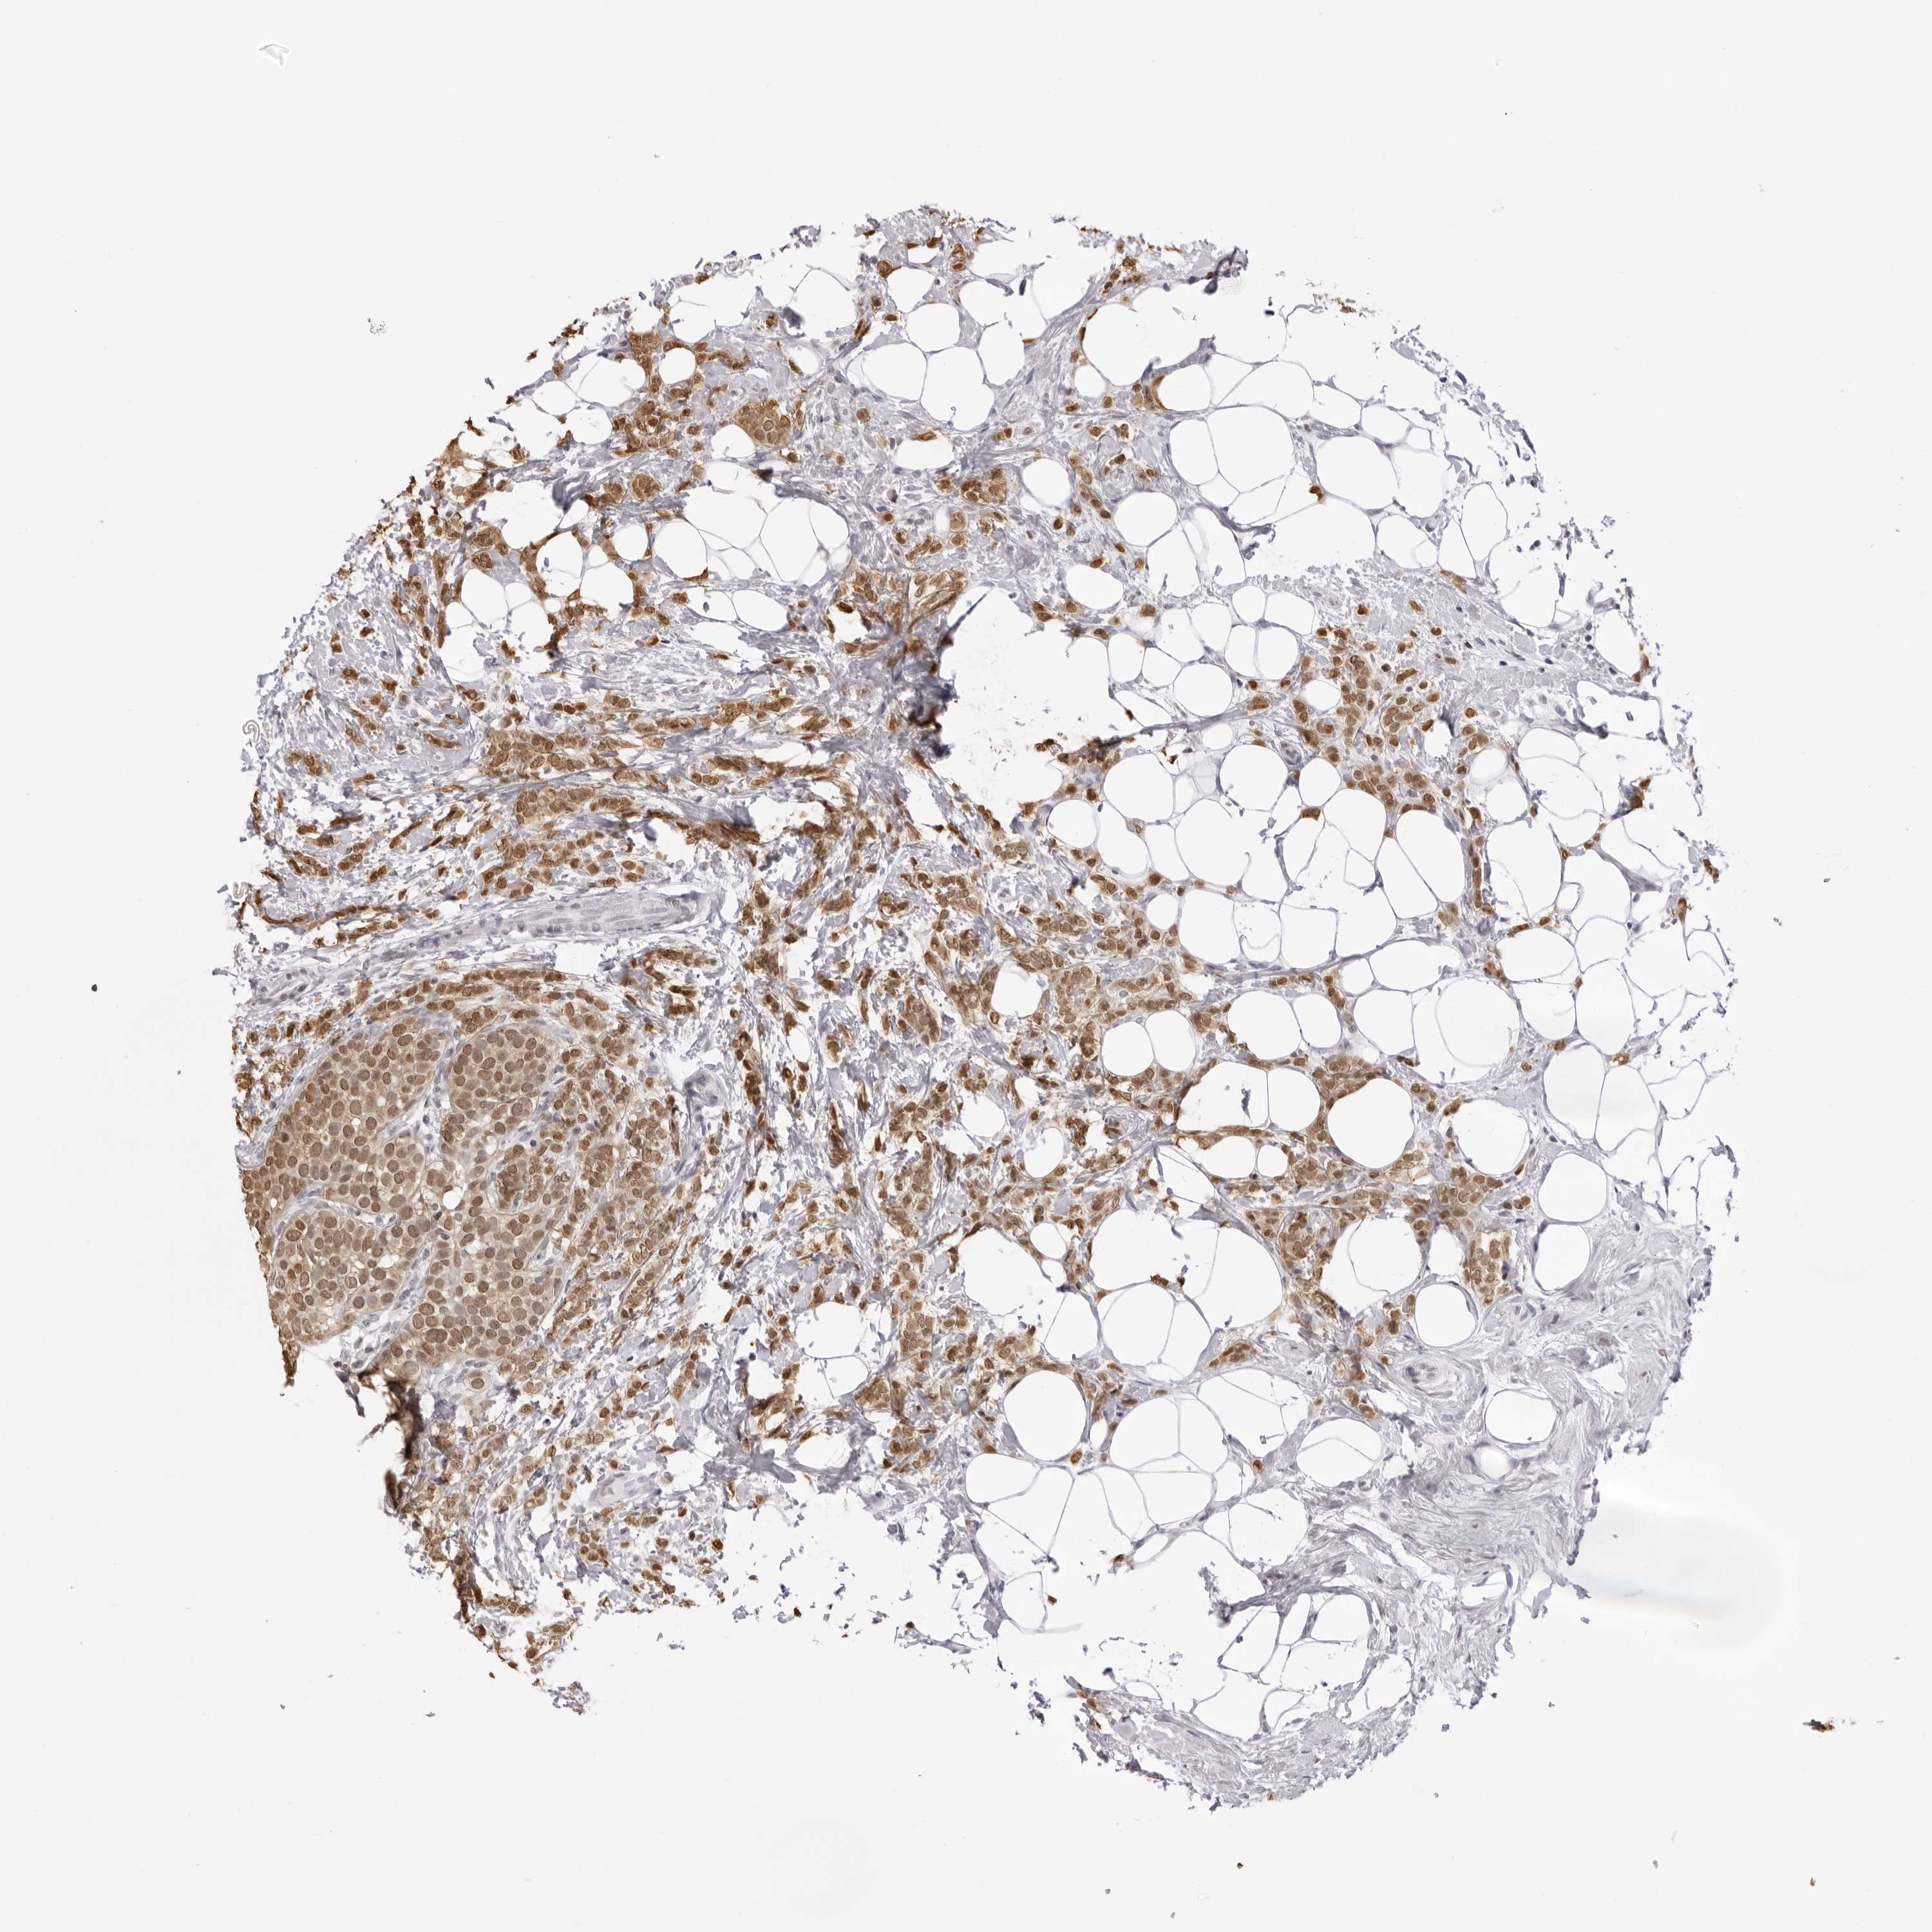

CANCER BREAST CANCER Show tissue menu

BRCA TCGA BRCA VALIDATION PROTEIN EXPRESSION